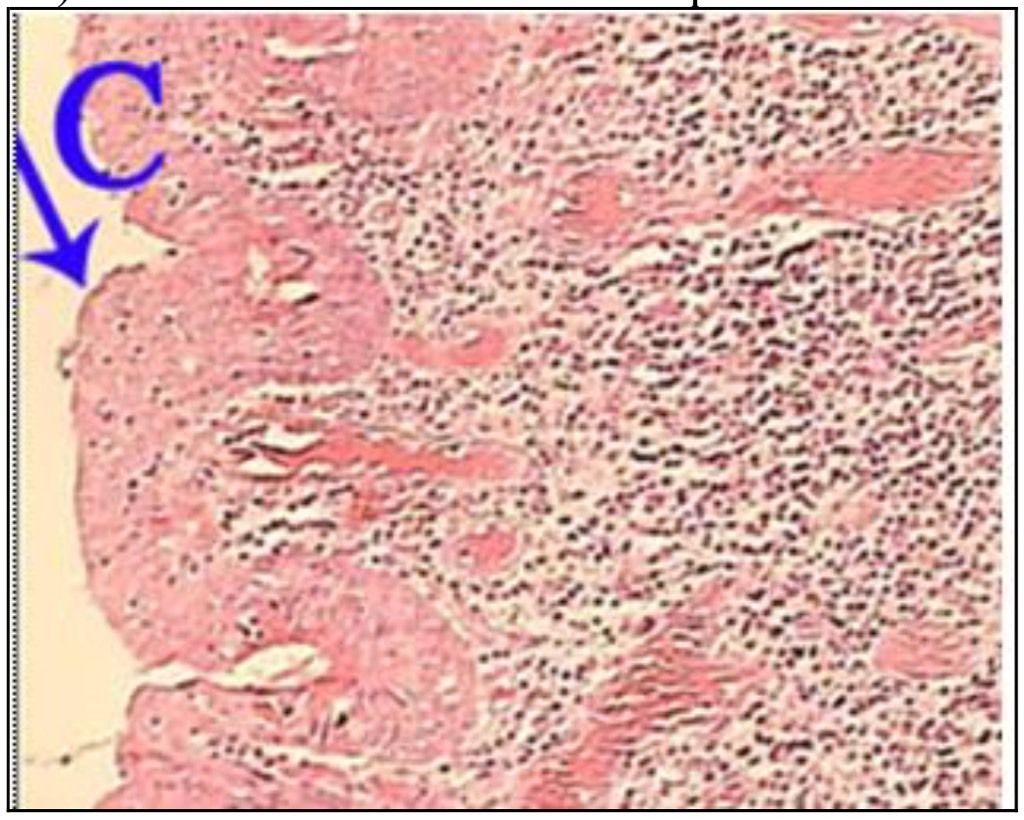

Question 1

Question

What is the correct answer at point A?

Answer

• - épithélium exocervical normal

• - membrane basale

• - cellules anormales

• - épithélium dysplasique sévère

• - massifs carcinomateux

Question 2

What is the correct answer at point B?

Question 3

What is the correct answer at point C ?